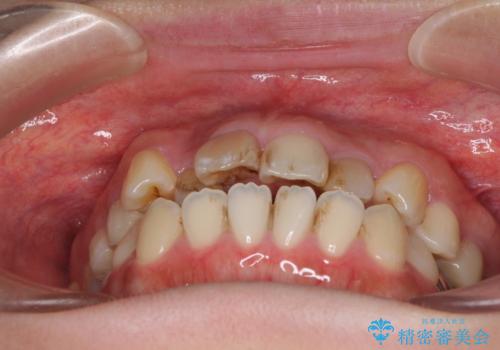

- 八重歯と前歯のデコボコ、開咬を気にして来院された患者様です。

抜歯矯正が必要であることはご自身で理解されており、目立たない装置をご希望であったので、上顎が裏側装置であるハーフリンガル装置にて治療を行うこととしました。

上顎前歯や下顎大臼歯に根管治療の必要な歯がいくつかあるため、矯正治療と並行して根管治療を行い、その後オールセラミッククラウンにて補綴治療を行うこととしました。